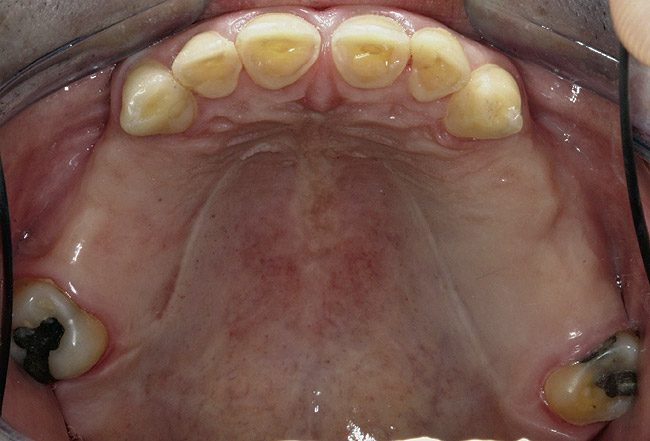

Figure 4  Intraoral occlusal view of maxillary dentition presenting excessive signs of wear.

Figure 4